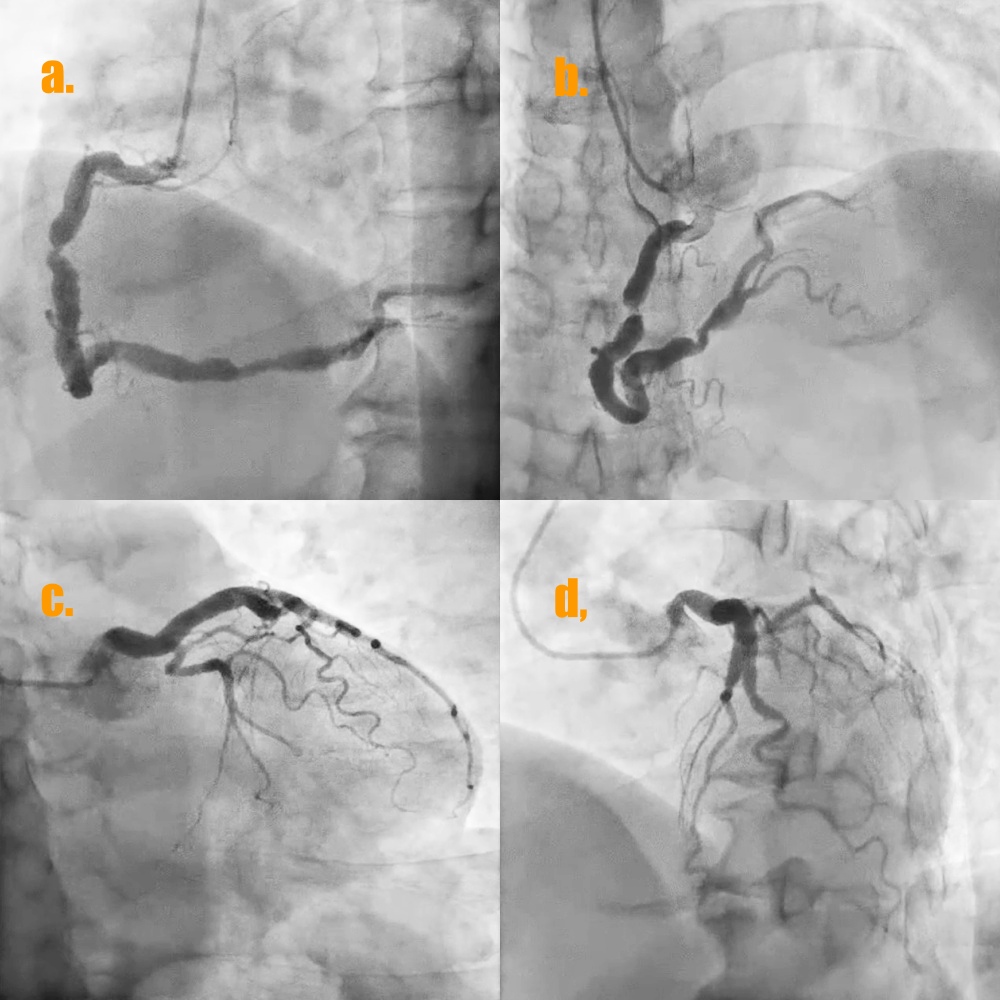

The coronary angiogram of the patient showed type 1 CAE of left anterior descending artery (LAD) and RCA (Fig 4a and 4d) and a significant stenosis with positive remodeling near coronary ectasia at middle RCA and another focal stenosis near coronary ectasia at distal RCA (video 1 and video 2) . In addition, there was much coronary thrombus with distal slow flow of coronary ectasia at distal RCA.

1. The 7 Fr left side radial sheath (Terumo; Glidesheath) was via left side radial artery approach and the guiding catheter was JR4 (Medtronic 7Fr) and the workhorse guidewire was Sion blue.2. Predilatation of the stenoses of distal part and middle part of RCA by the baloon Euphora 2.5x20mm and then IVUS was performed to assess the high risk plaque with adjacent CAE at middle RCA (Fig 5a and 5b) and stable plaque with adjacent CAE thrombus at distal RCA (Fig 5d and 5e).3. PCI of high risk plaque of middle RCA by direct DES stenting of Megatron (Boston ; 4.5x 12mm) under the extra-support of the guiding extension catheter of Telescope (Medtronic; 7 Fr) and lesion post-dilatation by larger balloon of NC Emerge (6.0x12mm) with 14 bars (Fig 6).

4.. PCI of distal RCA lesion first by direct drug-eluting stent (DES) Ultimaster-Nagomi (Terumo; 4.0x15mm) and then post-dilatation by larger balloon NC Emerge (6.0x8mm) with 16 bars. There was coronary thrombus at coronary ectasia of distal RCA with slow distal flow (Fig 5d). The intra-coronary thrombus suction device of Export Advance (Terumo; 6 Fr) was into CAE site of distal RCA for maneuver thrombus suction several times but still residual thrombus at CAE (Fig 6).

5. The final coronary angiogram of RCA has good distal flow (video 3) with stent optimalization (Fig 5c and 5f)